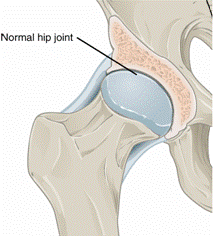

https://upload.wikimedia.org/wikipedia/commons/5/51/X-ray_of_a_normal_hip_joint.jpg

https://commons.wikimedia.org/wiki/File:X-ray_of_a_normal_hip_joint.jpg

Description English: For context, see: en:Hip pain

Description English:

·

Based off

Date 14

October 2015

Source Own work

Author CFCF